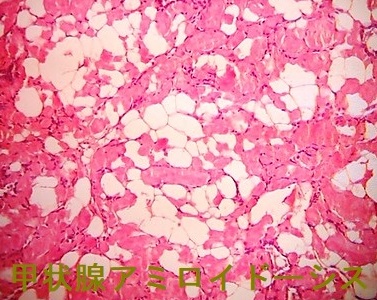

甲状腺アミロイドーシスの組織診

橋本病に合併した結節性甲状腺アミロイドーシスの病理組織標本では、

- アミロイド結節内の甲状腺濾胞構造は破壊され、異物反応や石灰化も存在する(第57回 日本甲状腺学会 P2-061 橋本病に合併した甲状腺amyloidosis の一例)

- アミロイド結節周囲の甲状腺組織には、リンパ球・形質細胞の炎症性細胞浸潤とリンパ濾胞形成を認めます。これらのリンパ球・形質細胞が、IgGのκ鎖を産生するのが原因では?と推察しますが、原因不明です。(第58回 日本甲状腺学会 P1-12-3 橋本病に合併した甲状腺限局免疫グロブリン軽鎖amyloidosisの一例)

- アミロイド沈着物は、細胞質内に小アミロイド滴を含む多数の組織球と多核巨細胞に囲まれる。しかし、血管壁にアミロイド沈着は無し。免疫組織化学検査により、アミロイドはアミロイドP成分、IgG、κ軽鎖が強陽性で、IgG、特にκ軽鎖(AL)が前駆体タンパク質と判明。[Acta Pathol Jpn. 1992 Mar;42(3):210-6.]。